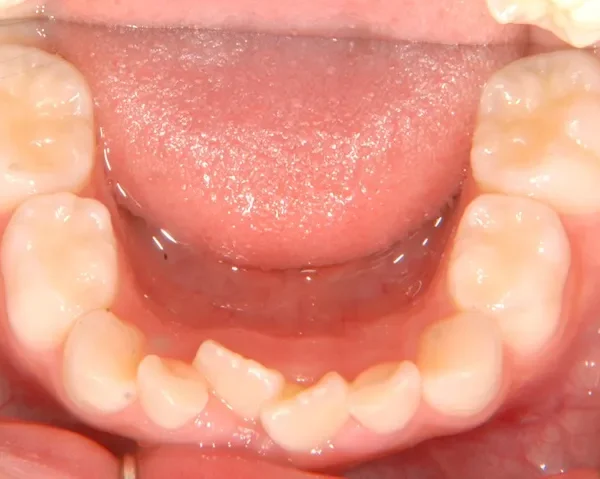

下の歯がずれて生えています。

こどもの歯は下の2本しか抜けていませんが、放っておくとガタガタがきつくなるので、早い段階からの治療としました。